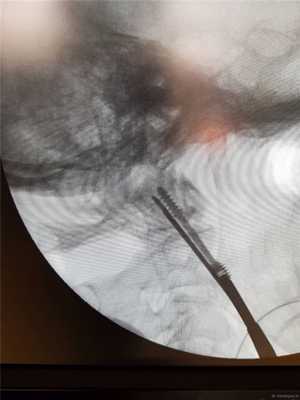

Спица проводится дрелью до верхушки С2. Затем так же проводится и вторая.

Затем первую спицу можно удалить и на ее место закрутить винт с двойной резьбой, предварительно измерив длину необходимого импланта по шаблону.